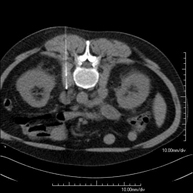

- Abdomen CT

Diagnostic test that involves obtaining high-definition anatomical images of the abdomen (liver, gallbladder, bile duct, pancreas, spleen, stomach, intestines, kidneys, vascular structures, bladder, uterus and ovaries, etc.) using CT (computed tomography) equipment. These images are then studied at a workstation capable of producing two-dimensional reconstructions in different spatial planes, and also 3D (volumetric) reconstructions. Most studies require the use of iodinated contrast to improve image definition.

- Abdominal and pelvic CT

Diagnostic test that consists of obtaining high-definition anatomical images (bone structures, vascular structures, liver, pancreas, gallbladder, kidneys, adrenal glands, spleen, small and large intestine, bladder, uterus and ovaries, prostate and seminal vesicles, ureters, etc.) using CT (computed tomography) equipment. Most studies require the use of iodinated contrast.